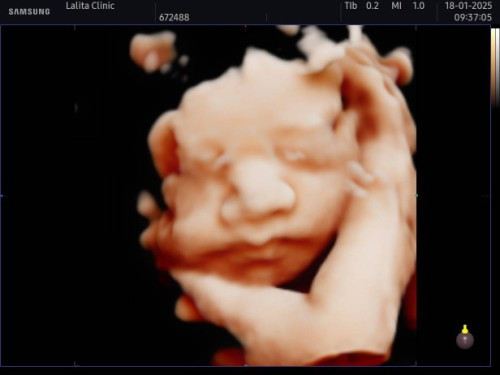

ลูกน้อย นน. เกินเกณฑ์ตลอด ล่าสุดไปหาคุณหมอ 1,875 กรัม 30 สัปดาห์

บำรุงดีมากค่ะ ทางนี้ 34w หนัก 2500 แล้วจ้า

ดูแบบนี้เสียเงินมั้ยคะแม่

เสียค่ะแม่ ทางคลีนิคเค้าจะให้ดูแค่รอบเดียว เพิ่ม 600 พร้อมได้ไฟล์ภาพค่ะ